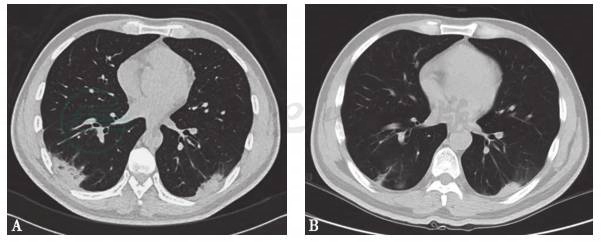

胸部CT:双肺野纹理增重紊乱,双下肺背段及后基底段近胸膜处多发片状密度增高影(图1)。鼻窦CT:左侧筛窦、双侧上颌窦轻度炎症。下肢CT动脉造影:右侧髂总动脉上段点状钙化,双胫后动脉节段性狭窄乃至闭塞可能。

图1 胸部CT

A:治疗前;B:治疗1个月后

患者有角膜溃疡、鼻窦炎、肺部阴影、下肢神经病变、肾小管损伤及贫血等多系统受累,红细胞沉降率、C反应蛋白等急性期反应物明显增高,完善各项检查后除外感染及肿瘤,结合患者病史、查体及辅助检查诊断为系统性血管炎。予甲泼尼龙500mg qd×3d激素冲击治疗,后减为甲泼尼龙40mg qd静脉滴注,同时予甲钴胺营养神经、卡马西平+曲马多止痛、琥珀酸亚铁补充造血原料等对症治疗,患者下肢疼痛症状明显好转,角膜溃疡基本愈合,但左足下垂、肌力无明显恢复,复查胸部CT提示肺部阴影较前稍加重,遂予利妥昔单抗375mg/m2 qw共4次,患者下肢疼痛症状消失,角膜溃疡愈合,左足下垂明显改善,右下肢肌力恢复至Ⅴ级,左下肢肌力恢复至Ⅲ级,C反应蛋白及红细胞沉降率降至正常。